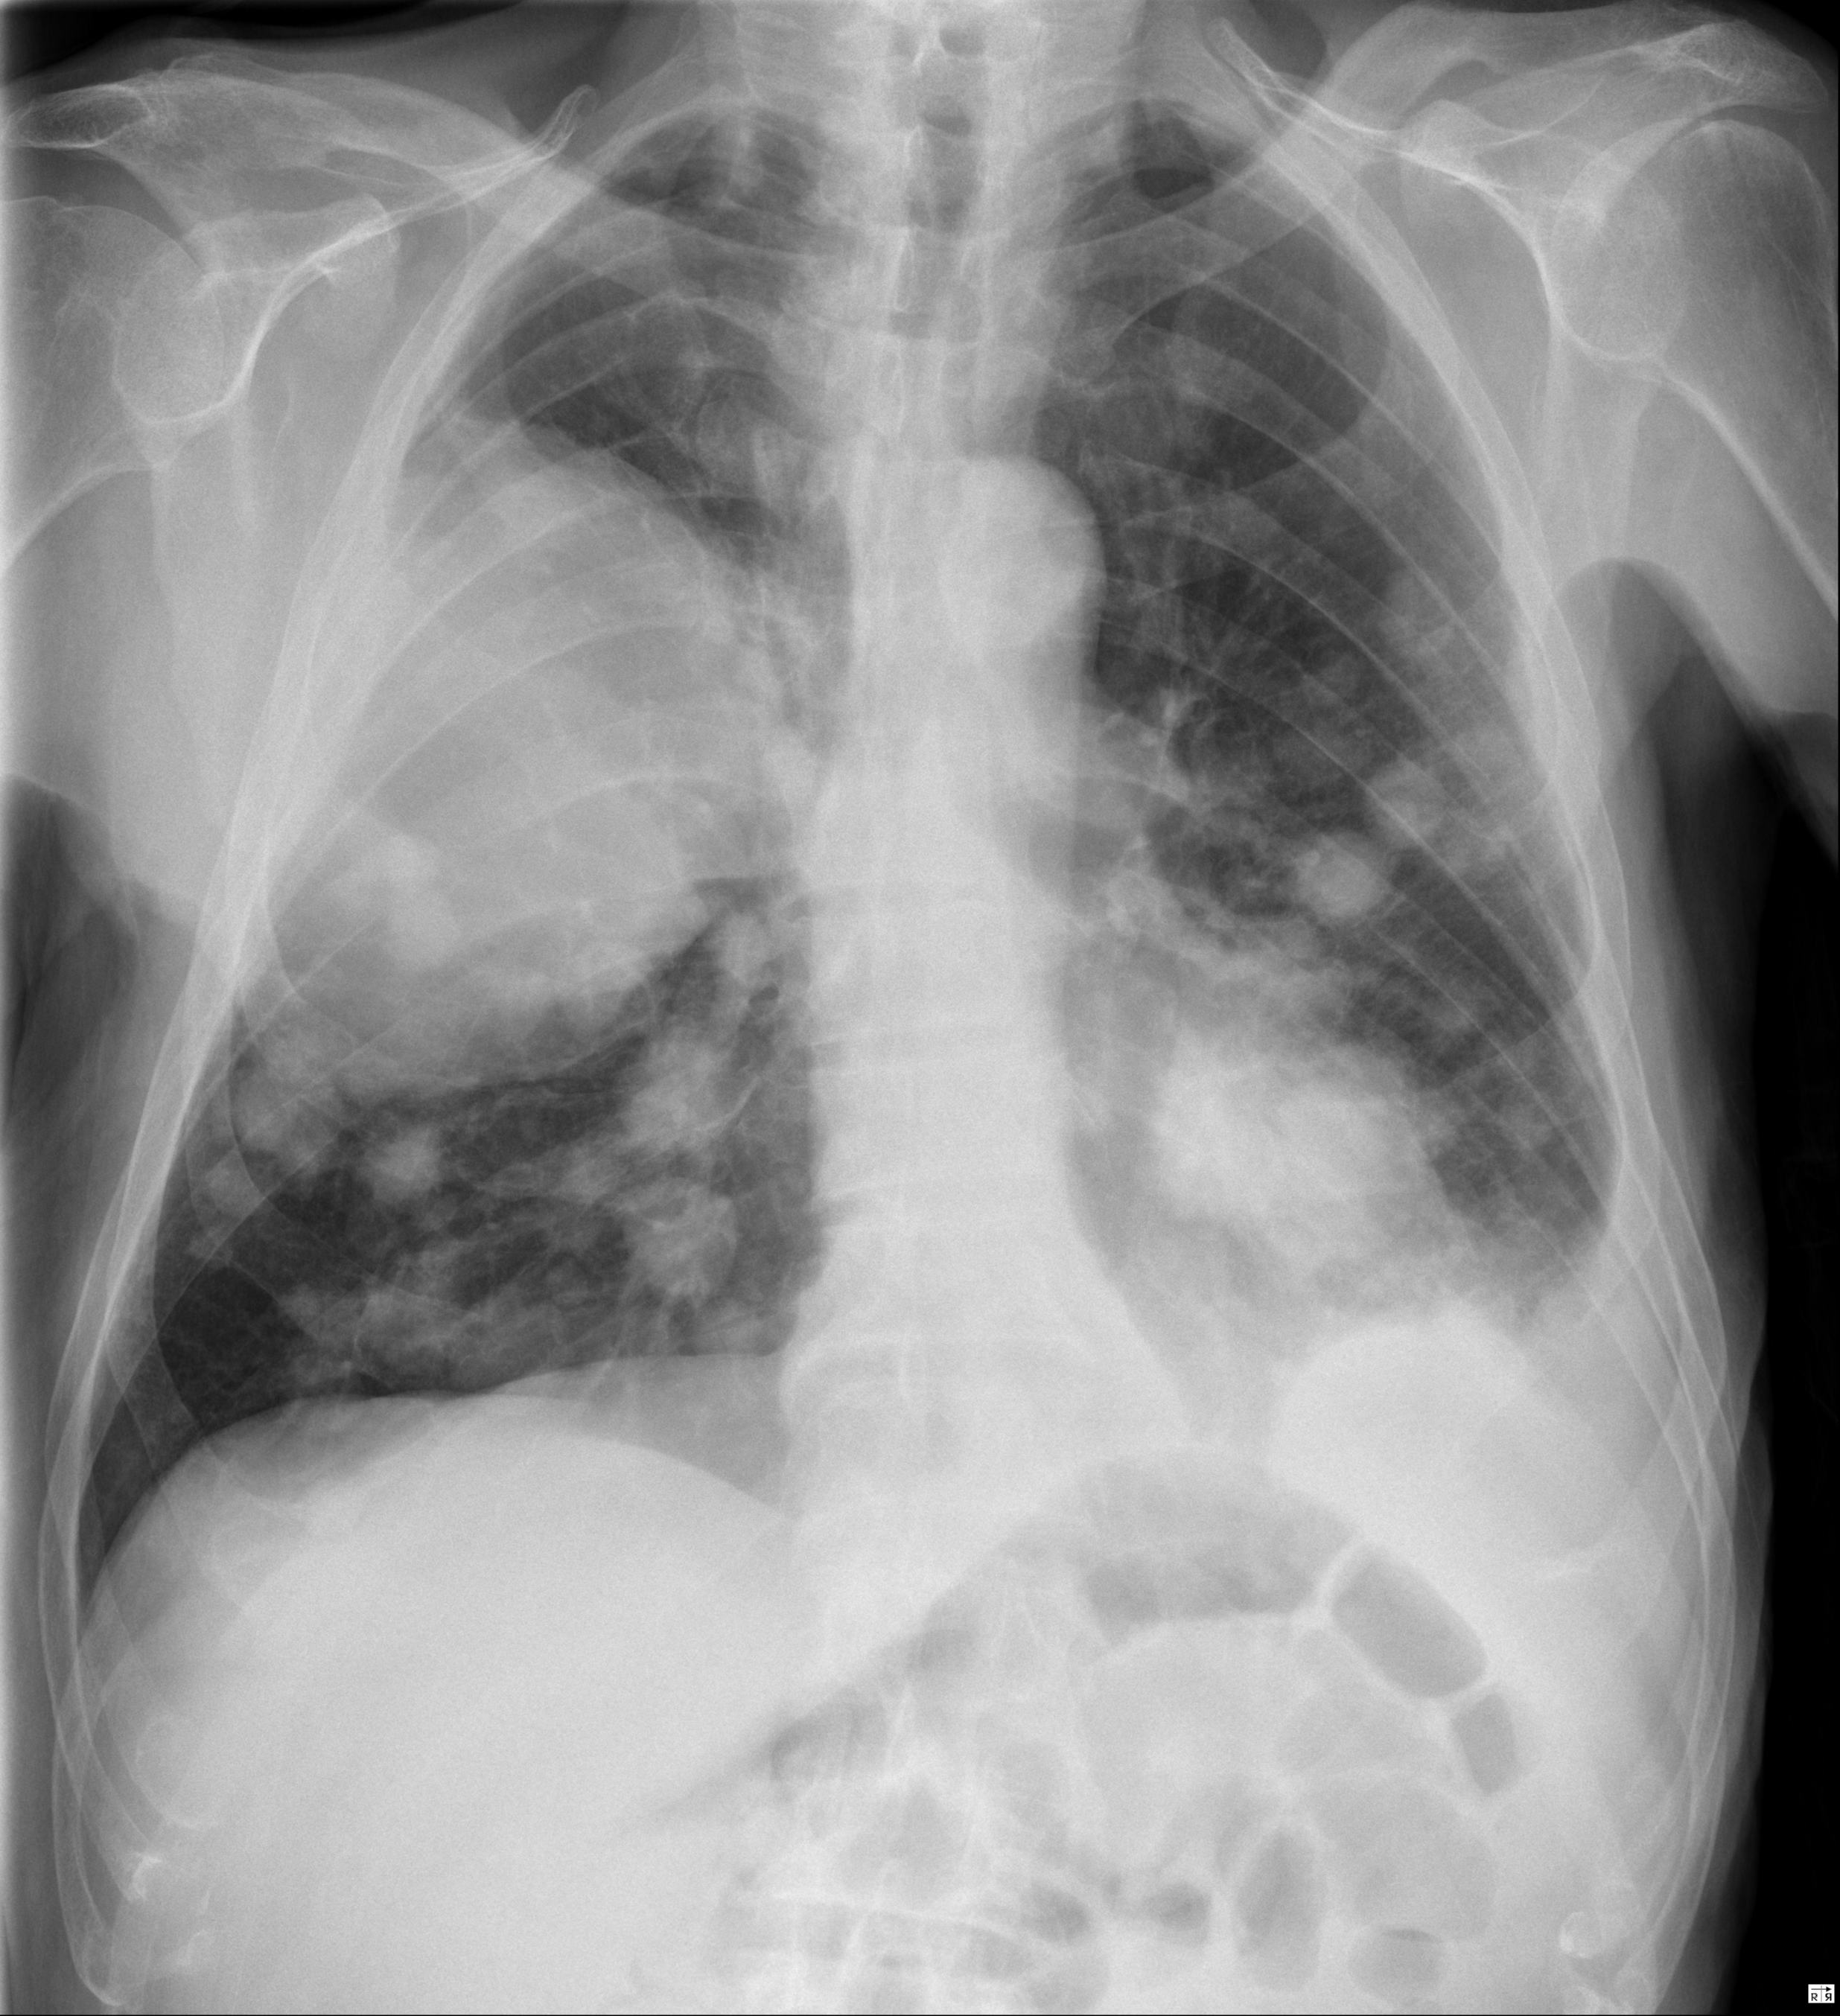

Lung Cancer Screening X Ray

Experience the clarity of Lung Cancer Screening X Ray with our curated collection of comprehensive galleries of images. featuring understated examples of photography, images, and pictures. designed to emphasize clarity and focus. Discover high-resolution Lung Cancer Screening X Ray images optimized for various applications. Suitable for various applications including web design, social media, personal projects, and digital content creation All Lung Cancer Screening X Ray images are available in high resolution with professional-grade quality, optimized for both digital and print applications, and include comprehensive metadata for easy organization and usage. Our Lung Cancer Screening X Ray gallery offers diverse visual resources to bring your ideas to life. Comprehensive tagging systems facilitate quick discovery of relevant Lung Cancer Screening X Ray content. Multiple resolution options ensure optimal performance across different platforms and applications. Time-saving browsing features help users locate ideal Lung Cancer Screening X Ray images quickly. The Lung Cancer Screening X Ray archive serves professionals, educators, and creatives across diverse industries. Instant download capabilities enable immediate access to chosen Lung Cancer Screening X Ray images. Whether for commercial projects or personal use, our Lung Cancer Screening X Ray collection delivers consistent excellence. Professional licensing options accommodate both commercial and educational usage requirements.